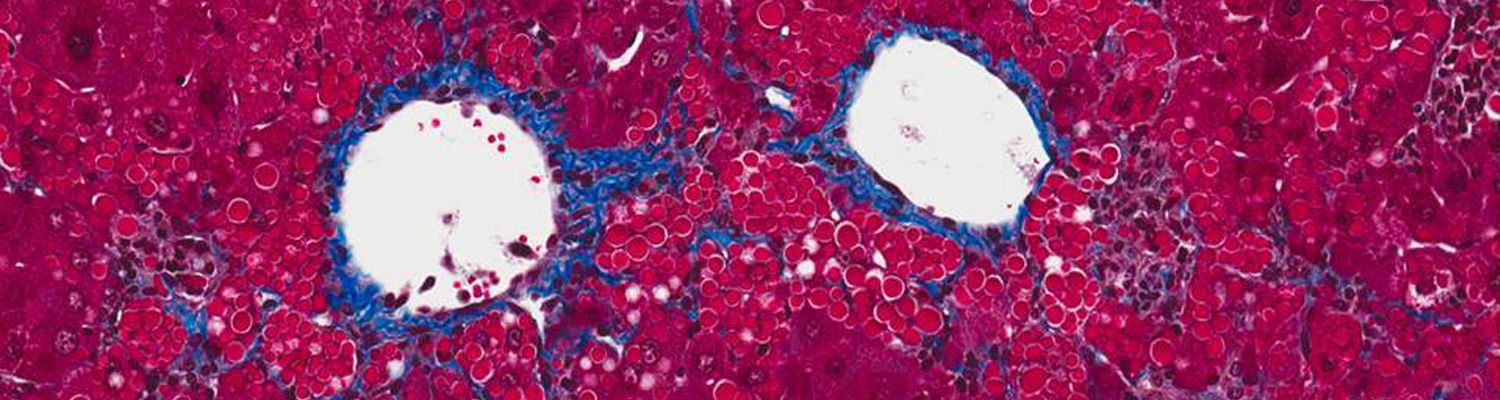

Mueller LabGene therapy for alpha-one antitrypsin deficiency

Alpha-one antitrypsin deficiency has been the focus of our lab since its inception. Building up on the work of Dr Terry Flotte directed towards production of the normal AAT protein (see the results of our clinical trial here), we developed a dual function vector that not only allows production of the normal AAT but also silences the mutated, toxic Z-AAT protein.